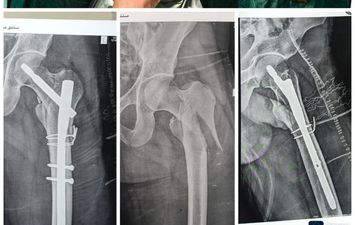

حضر إلى قسم طواريء مستشفى اليوم الواحد بمركز أشمون التابعة لمديرية الصحة بمحافظة المنوفية مريض يبلغ من العمر 28 عامًا وهو يعانى من كسر مضاعف أعلى عظمة الفخذ الأيسر إثر ادعاء السقوط من أعلى.

تم استقبال الحالة بسرعة وحجز المريض فورًا، ثم تحضيره للعمليات دون أي تأخير، ودخل المريض غرفة العمليات في نفس اليوم، حيث أُجريت له جراحة دقيقة (Open Reduction & Internal Fixation) وتم تثبيت الكسر باستخدام مسمار نخاعي جاما بنجاح.

وذلك بتواجد الفريق الطبي الدكتور محمود العيسوي أخصائي جراحة العظام، والدكتور مصطفى سامح نائب جراحة العظام، والدكتور أحمد عبد العاطي استشاري التخدير، وصفاء بيومي تمريض العمليات، ومي مسعد مسؤول أشعة ال C_ARM

تحت إشراف الدكتور تامر طاحون مدير العمليات، والدكتور حنان شعير مدير المستشفى.